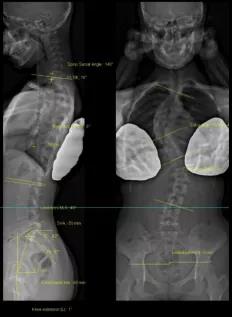

法國EOS X射線影像采集系統(tǒng)

?諾貝爾物理學獎的新型X射線探測技術;

?實現(xiàn)了人體1:1真實成像;

?是非拼接全脊柱、全下肢一次性成像X線設備;

?僅需0.05mSv(約一張胸片的劑量)即可完成全脊柱正側位成像。

?正側位全長影像一次掃描成像的優(yōu)點:負重位正交同步拍攝、線性掃描1:1全長片、動態(tài)自動增益控制;

?雙球管正側位同步拍攝:一次掃描同時獲得正、側位影像,消除兩次拍攝的系統(tǒng)誤差;

?精準的線性掃描:幫助醫(yī)生對脊柱、關節(jié)等相關骨骼疾病進行術前診斷、制定手術計劃、評估手術效果、跟蹤隨訪以及相關科研工作;

?不失真高質量圖像:全身視圖1:1。

脊柱側彎